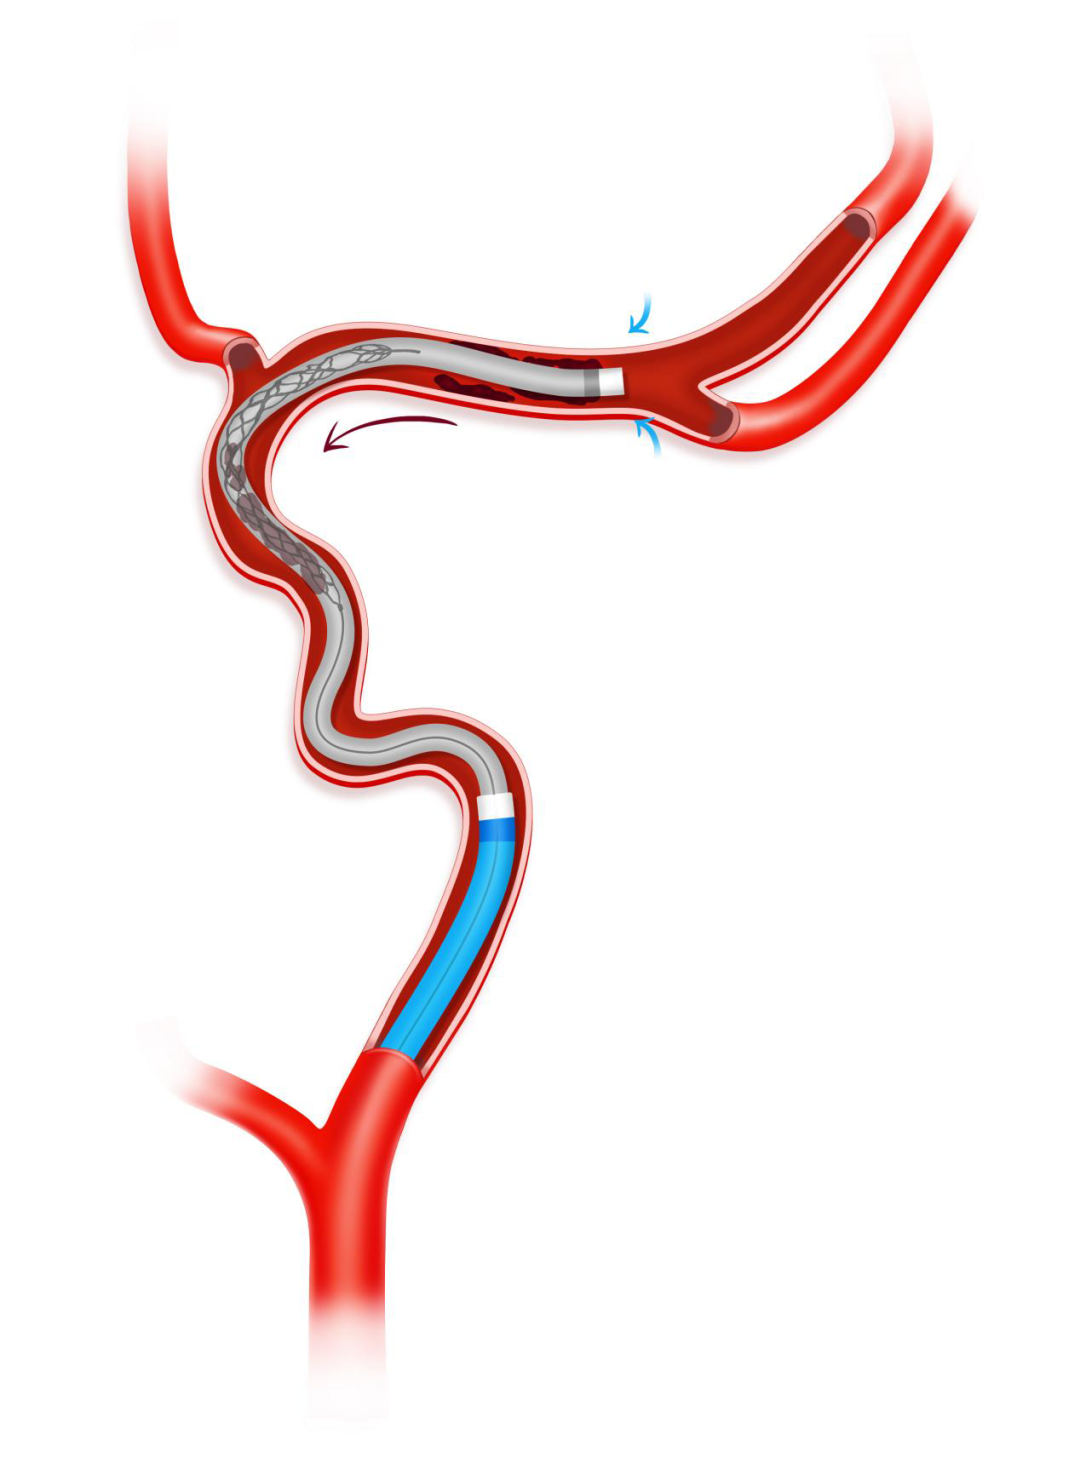

AOSIS技术(Acute large vessel OccluSion recanalization with the Intracranial protection of Stent retriever,颅内取栓支架保护下的急性大血管闭塞开通术)是基于加奇生物 Syphonet®取栓支架的独特设计特点而衍生出的针对急性大血管闭塞开通实施颅内保护的技术,在颅内动脉急性闭塞,血栓抽吸导管新手很难到位接触抽吸血栓,取栓过程容易栓子逃逸问题,利用3.0*25mm Syphonet®取栓支架作为颅内保护装置在闭塞血管远端锚定,支架远端有网篮设计,可以捕获逃逸血栓而起到保护伞的作用,近端跟进Tethys AS®血栓抽吸导管至血栓近端,关闭滴注打开血栓抽吸导管Y阀状态下越过血栓,回收支架至血栓抽吸导管内,最后将Syphonet®及Tethys AS®整体撤出。同时,Syphonet®取栓支架适配0.017、0.021inch的微导管,较小的微导管超选后,可直接将支架输送至远端释放,锚定支撑能力较强。

3.0*25mm Syphonet®取栓支架远端保护,预防抽吸术中血栓逃逸,提高手术安全性。

Syphonet®取栓支架输送导丝作为工作支撑导丝,让Tethys AS®血栓抽吸导管通过性能提高,血栓抽吸导管到位接触和越过血栓能力大大提高。目前的取栓手术中,血栓抽吸导管能不能迅速到位接触血栓和越过抽吸是血管快速再通成功的关键。

如果是夹层和ICAS病变情况下,结合BASIS避免反复交换,精简手术操作,减少手术时间。

同时选用较小的3.0*25mm Syphonet®取栓支架也减少了对血管的损伤,降低支架取栓导致血管内皮剥脱、夹层、穿支血管损伤和撕裂等并发症的风险。

沿17或21系列微导管输送并释放3.0*25mm Syphonet®取栓支架,支架近段覆盖大脑中动脉闭塞病变部位,支架远端到达大脑中动脉M2。利用Syphonet®取栓支架的锚定作用和远端防血栓逃逸保护作用。

Syphonet®取栓支架锚定作用下跟进Tethys AS®血栓抽吸导管,靠近血管病变处开始关掉滴注,打开血栓抽吸导管Y阀后,越过大脑中动脉闭塞处到达大脑中动脉M1段末端。

负压下将Syphonet®取栓支架撤回Tethys AS®血栓抽吸导管内。

负压下将Syphonet®取栓支架和Tethys AS®血栓抽吸导管一起撤出,造影确认再通后结束手术。

手术示意图

本例全程在局麻下完成,术中我们采取AOSIS技术来进行本例开通血管,远端取栓支架锚定,利用Syphonet®取栓支架抓捕篮作为保护,近端Tethys AS®血栓抽吸导管关闭滴注越过血栓进行抽吸取栓,这样使血栓抽吸导管迅速到位充分接触血栓,并且远端有取栓支架保护,减少血栓逃逸的风险,极大提高血管再通效率,实现安全开通。